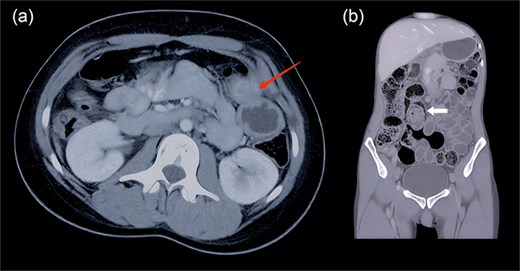

On clinical examination, the child appeared well but was irritable. Abdominal examination revealed a soft, distended, and non-tender abdomen. Digital rectal examination showed an empty rectum. The rest of the systemic examination was unremarkable. Based on the clinical presentation, a provisional diagnosis of Hirschsprung’s disease was considered. The laboratory investigation revealed anemia (hemoglobin: 7 g/dl) [reference: 9–14 g/dl] and hypoalbuminemia (serum albumin: 2.3 g/dl) [reference: 3.3–5 g/dl]; the rest of the parameters were within normal limits. Ultrasound was inconclusive, and contrast enema was not performed due to clinical urgency and patient clinical condition. Contrast-enhanced computed tomography was planned before surgery, which revealed a Tubular structure measured ~12.2 × 3.2 cm which located parallel to the native colon from terminal ileum to pelvis. No communication with the native lumen lying next to the colon, running parallel, and sharing its wall. It had fluid inside and did not take contrast, suggestive of a colonic duplication cyst (Fig. 1a and b).

(a and b) Contrast-enhanced computed tomography (axial and coronal view) shows a tubular structure lying next to the colon of size 12.2 × 3.2 cm (arrow 1), running parallel, and sharing its wall (arrow 2). It had fluid inside and did not take contrast.